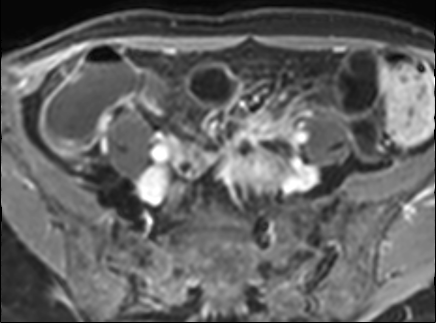

Kiểu ngấm thuốc phân lớp tại trực tràng kèm một ít mờ mỡ xung quanh trên hình ảnh T1 axial sau tiêm thuốc tương phản từ (mũi tên). Tình trạng viêm liên tục với kiểu ngấm thuốc đồng nhất có thể thấy tại đại tràng sigma (mũi tên xanh lá). Ngoài ra, có một nang phần phụ bên phải với viền ngấm thuốc (đầu mũi tên).

Kiểu ngấm thuốc

phân lớp

Kiểu này gợi ý hoạt động bệnh nặng hoặc bệnh mạn tính kéo dài (4,5).

Hình ảnh ba lớp được tạo ra do niêm mạc và thanh mạc ngấm thuốc mạnh trong khi lớp giữa không ngấm thuốc, bao gồm lớp dưới niêm mạc và lớp cơ.

Lớp giữa này có thể chứa mỡ, phù nề hoặc mô xơ.

Có thể phân biệt các thành phần này bằng chuỗi xung T2 có fat-sat.